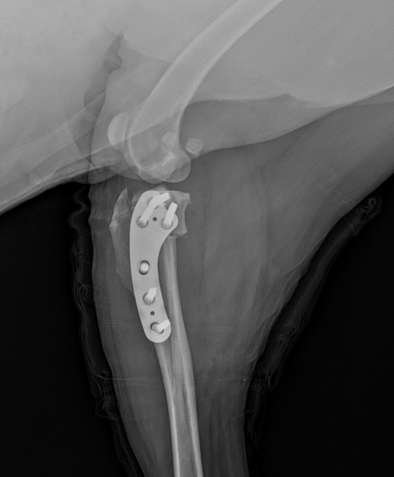

TPLO 십자인대 수술절뚝거리는 증상으로 내원!

TPLO 수술 후 건강한 일상으로 복귀 -